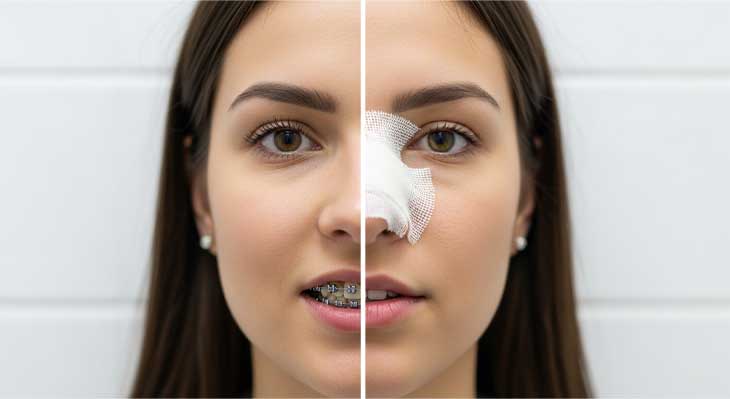

دندان اضافه